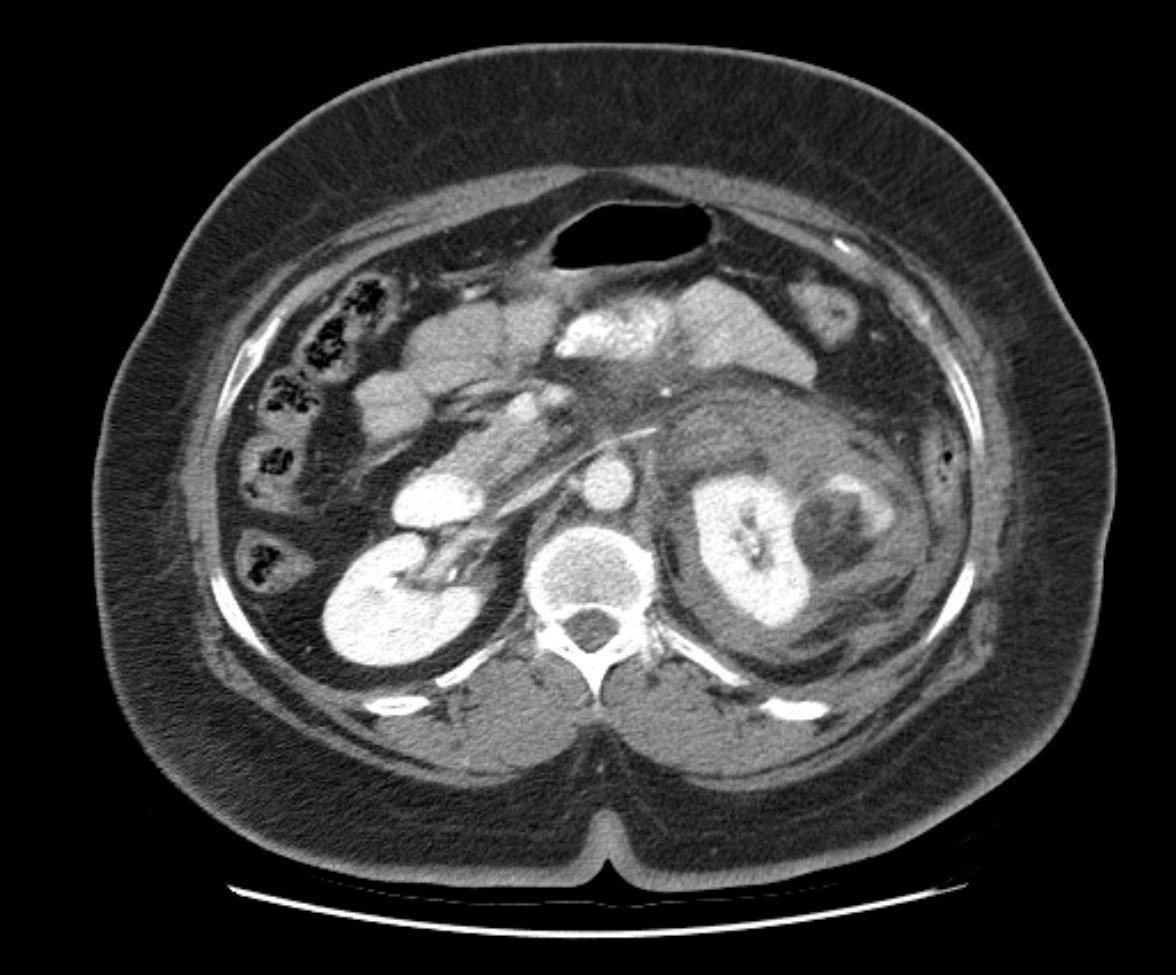

19F Hypertensive

kypokalaemia

elevated aldosterone

Juxtaglomerular Tumor (Reninoma)

Reninoma is a tumour of the cells of the juxtaglomerular apparatus that produces excessive amounts of renin, resulting in a secondary form of hyperaldosteronism, manifesting clinically with hypertension (HT) and hypokalaemia1. This renal tumour is predominant in females, with a peak incidence between the second and third decade of life and, although uncommon, it is a treatable cause of HT2. It should be suspected in any patient with refractory HT associated with hypokalaemia and high levels of aldosterone.

We present the first case of reninoma reported in Argentina in a young woman with refractory HT and hypokalaemia.

In 1967, Robertson et al.6 reported the first renin-producing tumour. Kihara et al. later called them “juxtaglomerular cell tumours”7. These tumours are very uncommon, with their incidence peaking between the second and third decade of life and they are predominantly found in females, originating in the myoendocrine cells of the renal juxtaglomerular apparatus, although the production of renin by different tumours has also been demonstrated, such as Wilms tumours, carcinoid tumours, renal oncocytoma and renal cell carcinoma8,9. In accordance with the presence or absence of symptoms, JCT may occur as: a “typical” variant in the majority of cases and manifests with HT, hypokalaemia, high plasma renin and secondary hyperaldosteronism; an “atypical” variant, in which HT is not accompanied by hypokalaemia; and a third “non-functioning” variant, which occurs without HT and with normal levels of potassium10,11.

Plasma renin activity (PRA) and plasma aldosterone (PA)